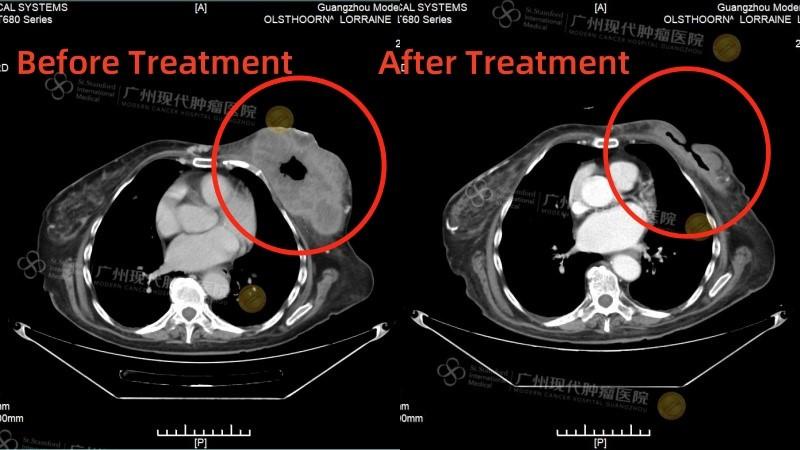

История пациента: Ляззат, 47 лет, юрист, Казахстан. Диагноз: Рак молочной железы IV стадии с множественными метастазами в печень. Тактика лечения: Комбинация интервенционной терапии (химиоэмболизация) и микроволновой абляции (МВА). Результат: Полная регрессия опухоли в молочной железе, уменьшение метастазов в печени более чем вдвое, нормализация функции печени и онкомаркеров. Неожиданная находка: когда привычный мир рухнул Ляззат - успешная женщина из Казахстана, юрист, привыкшая решать сложные задачи в суде, в начале 2025 года столкнулась с самым тяжелым делом в своей жизни. Обследование, начатое из-за усталости и скачков давления, привело к шокирующему открытию: во время УЗИ случайно обнаружили опухоль в печени, а вскоре она сама нащупала уплотнение в груди. Диагноз прозвучал как приговор: рак молочной железы IV стадии с множественными метастазами в печень. Местные врачи настаивали на единственном, по их мнению, варианте: длительном курсе химиотерапии и обязательной мастэктомии - удалении молочной железы. Принципиальное решение: сохранить не только жизнь, но и себя Для сильной и осознанной женщины это было неприемлемо. «Грудь - это не просто орган, это часть моей женской идентичности. Я никогда не соглашусь на ее удаление и должна найти лучшее решение», - так Ляззат сформулировала свою позицию. Она обратилась в клиники Турции, Индии, Южной Кореи, но нигде не получала гарантий, что лечение сможет победить рак и сохранить грудь. В момент отчаяния надежду подарила подруга, порекомендовавшая St.Stamford Modern Cancer Hospital Guangzhou и его малоинвазивные подходы.

Результат превзошел все ожидания. После двух курсов комбинированного лечения: • Опухоль в молочной железе полностью исчезла. • Метастатические очаги в печени уменьшились более чем в два раза. • Функция печени и уровень онкомаркеров (РЭА, СА153) пришли в норму. • Вернулись силы, ушла постоянная усталость. Уже в третий визит в Гуанчжоу Ляззат приехала одна, чувствуя себя настолько хорошо, что могла перенести длительный перелет и вернуться к привычной жизни. Ценить настоящее: урок, выученный с достоинством. Сегодня Ляззат не только победила болезнь, но и переосмыслила жизнь. Она благодарна команде врачей в Гуанчжоу за теплоту, поддержку и профессиональную помощь. Она активно практикует дыхательные методики и медитацию для борьбы со стрессом и участвует в жизни клиники. «Жизнь - это дар. У нас она только одна, и мы должны ее ценить, - говорит Ляззат. - Не следует переутомляться, злиться и беспокоиться. Живите настоящим и наслаждайтесь жизнью. В этом ее смысл!» Ее история - это вдохновляющий пример того, как современная медицина позволяет отстоять свое право на целостность и качество жизни даже в самой сложной ситуации.